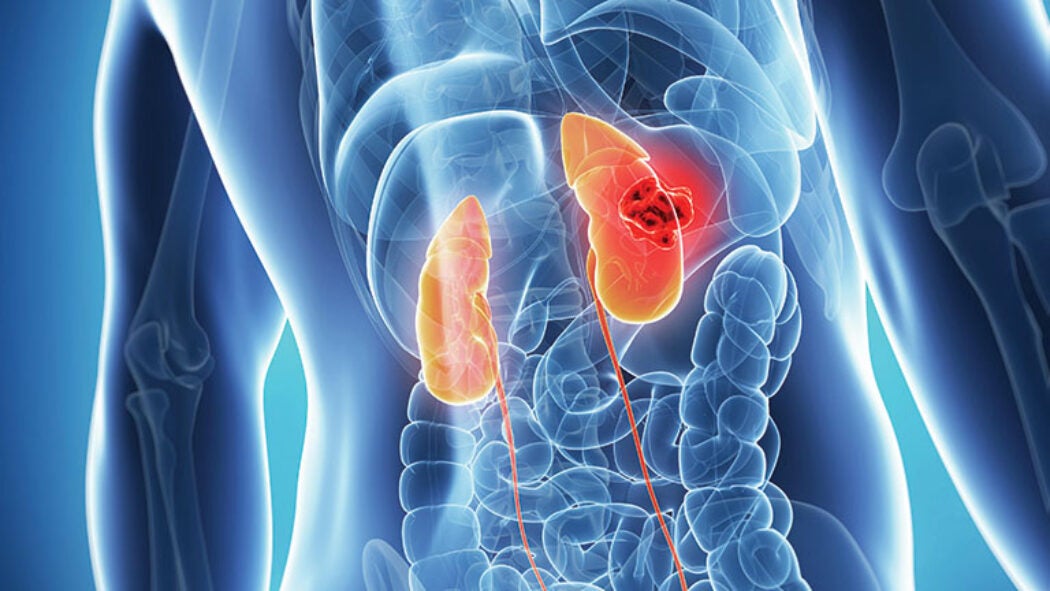

imaging of Ewing sarcoma: a pink sea anemone looking object

Because the disease often affects teens, side effects like infertility from current treatments are hard to bear. New research at Georgetown offers hope for an alternative.